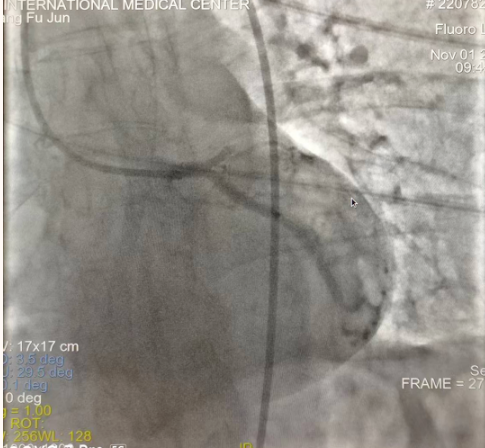

閉塞的血管再通時(shí)間取決于急救時(shí)長(zhǎng)、轉(zhuǎn)運(yùn)時(shí)長(zhǎng)和治療時(shí)長(zhǎng),在前兩方面,醫(yī)院已為患者爭(zhēng)取了最短時(shí)間?;颊呒覍龠h(yuǎn)在陜北,雖然已在趕來(lái)的路上,但最快抵達(dá)西安也要3小時(shí),在與患者家屬電話溝通同意急診手術(shù)后,醫(yī)療總值班代家屬簽字,康曉軍在請(qǐng)示心臟病醫(yī)院王海昌院長(zhǎng)及心臟內(nèi)科CCU尚福軍主任后,積極進(jìn)行術(shù)前準(zhǔn)備。在沒有家屬陪同、沒有交費(fèi)、沒有辦入院手續(xù)的情況下,患者經(jīng)胸痛中心綠色通道被送往心臟冠脈介入手術(shù)室,打通了完全閉塞的心臟前降支近段血管。